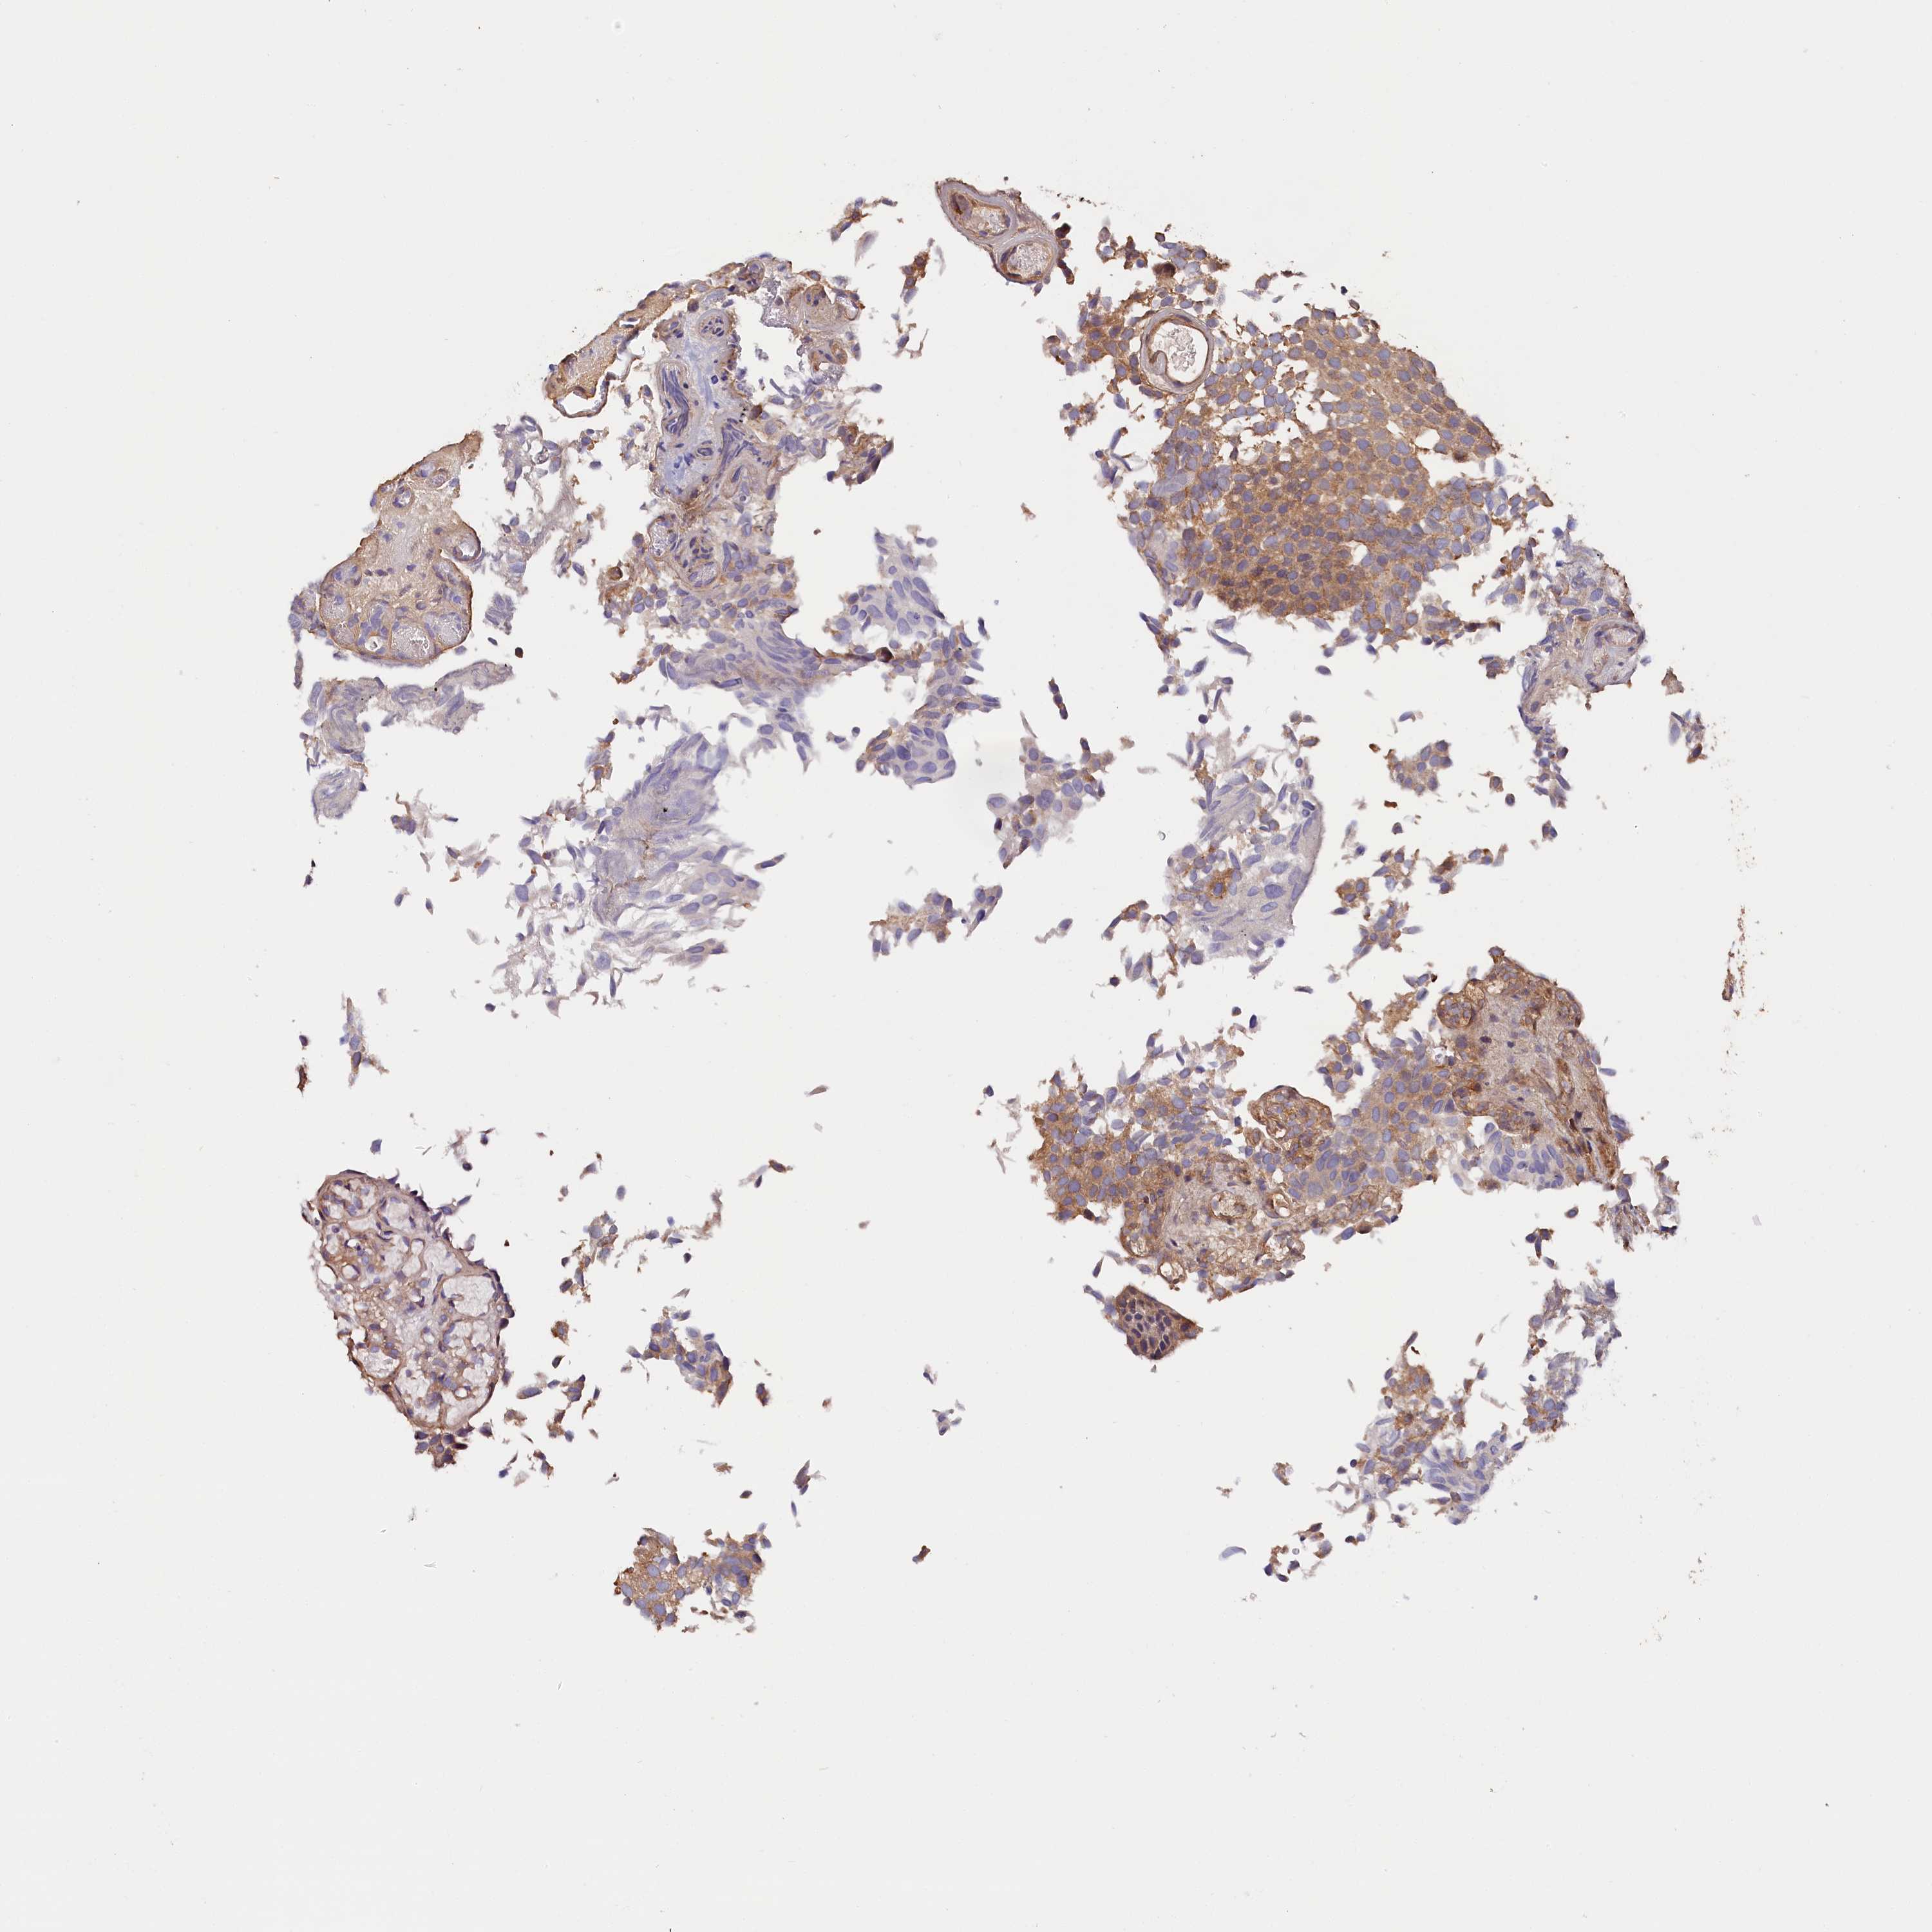

UROTHELIAL CANCER - Protein expressioni

A mouse-over function shows sample information and annotation data. Click on an image to view it in a full screen mode. Samples can be filtered based on level of antibody staining by selecting one or several of the following categories: high, medium, low and not detected. The assay and annotation is described here.

Note that samples used for immunohistochemistry by the Human Protein Atlas do not correspond to samples in the TCGA dataset.

Antibody stainingi

Antibody staining in the annotated cell types in the current human tissue is reported as not detected, low, medium, or high, based on conventional immunohistochemistry profiling in selected tissues. This score is based on the combination of the staining intensity and fraction of stained cells.

Each image is clickable and will lead to virtual microscopy that enables deeper exploration of all samples and also displays staining intensity scores, fraction scores and subcellular localization as well as patient and tissue information for each sample.

Antibody HPA041165

Antibody HPA041839

Staining

High

Medium

Low

Not detected

Intensity

Strong

Moderate

Weak

Negative

Quantity

>75%

75%-25%

<25%

None

Location

Nuclear

Cytoplasmic/membranous

Cytoplasmic/membranous,nuclear

Urothelial carcinoma, High grade

Urothelial carcinoma, Low grade